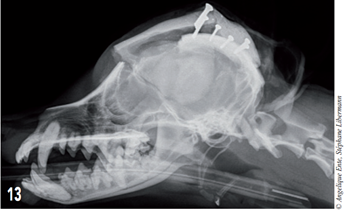

Les radiographies post-opératoires (figures 13 et 14) montrent que la couverture de l’encéphale antérieur est satisfaisante.

Figure 13 – Radiographie post-opératoire du crâne en décubitus latéral.